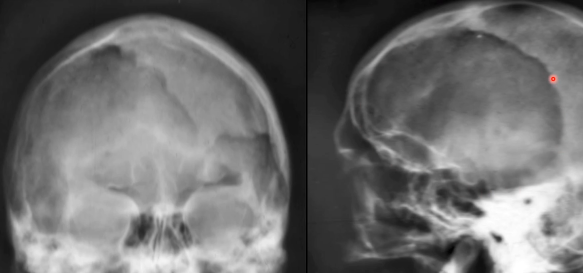

- Lyse craniale

Cotton Wool Skull

- Patchs de sclérose dans un crane lytique

- Risques d’atteinte neurologique à la base du crâne